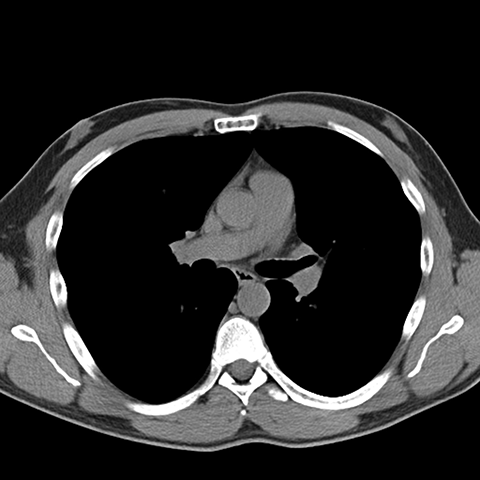

Normal Unenhanced CT (Mediastinal Window) [4 of 8]